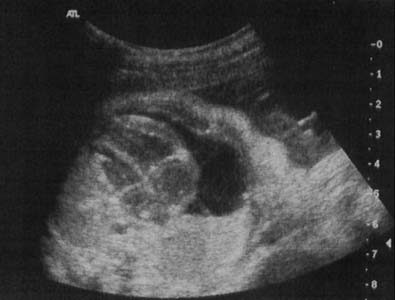

Kyste pleuro-péricardique